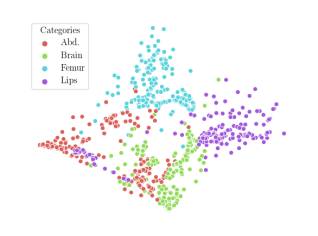

We compare the -distance of categorical features and domain features. Fig. 5 (a) shows that domain difference is higher in domain features than in categorical features. This indicates that domain features contain more domain information whereas categorical features are more domain-invariant. Fig. 6 shows the t-SNE plot of categorical features in both domains for MIDNet. From Fig. 6 (a), we observe that the categorical features learned by MIDNet enable the anatomical classification. Fig. 6 (b) shows that the learned categorical features are domain-invariant.

In addition, we utilize t-SNE plots for feature visualization in Fig. 10. Comparing Fig. 10 (a) and Fig. 10 (b), we observe that with mutual information disentanglement, (1) samples from the same category are more tightly clustered (see the top row) and (2) the source domain and the target domain are overlap more (see the bottom row). This indicates that mutual information disentanglement is important for learning categorical-focused and domain-invariant features. Fig. 10 (a), (c)-(d) show that the proposed method outperforms other state-of-the-art methods for learning category-discriminative and domain-invariant features, especially for unseen categories in the target domain (e.g., (a) vs. (d)).